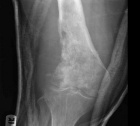

59 year old female complains of knee pain for two months

ESR 112mm/hr

CRP 156 mg/l

WBC 14.6

Zoom image: Radiological image Radiological image.